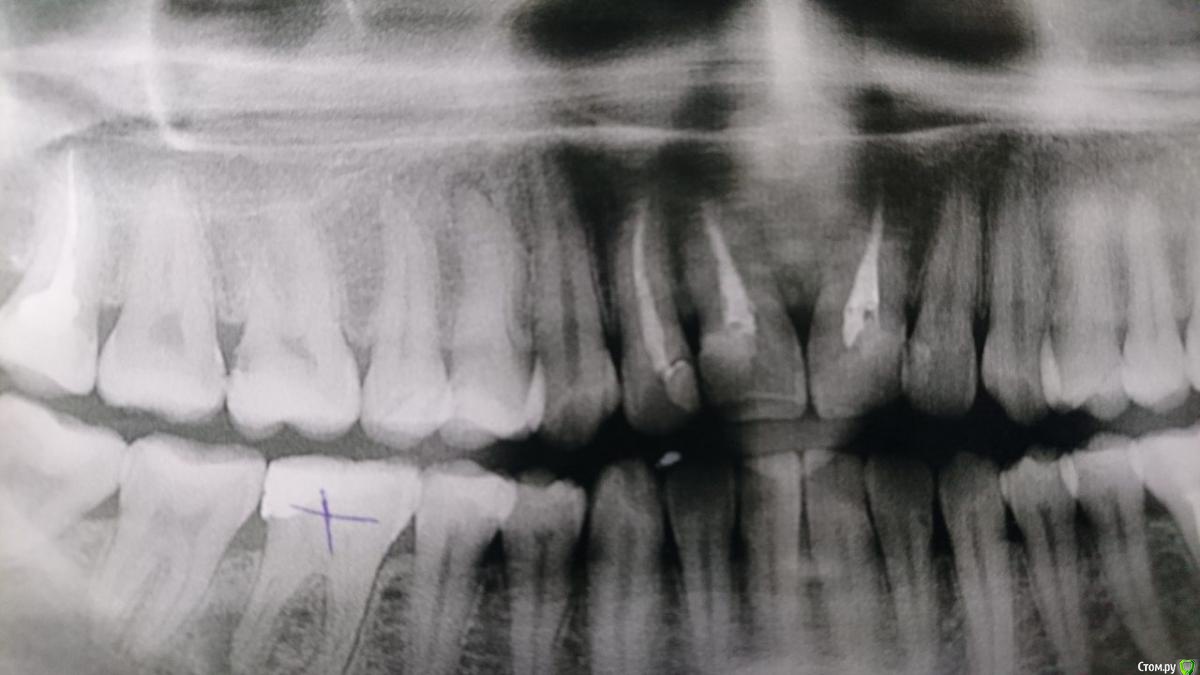

Юлия Сергеевна 85 Опубликовано 10 февраля, 2017 Поделиться Опубликовано 10 февраля, 2017 (изменено) Здравствуйте, коллеги, девушка 30ти лет, зуб 1.4... Не найду каналы, литр белодеза, ультразвук, погнутые 8 и 10 римеры..кстати, удалили 4.6, распилили, медиальных нет, там прям стеклянно все. Советуйте, плиз Изменено 10 февраля, 2017 пользователем Юлия Сергеевна 85 Ссылка на комментарий

vse32 Опубликовано 10 февраля, 2017 Поделиться Опубликовано 10 февраля, 2017 Поискать каналы не в привычных местах а чуть медиальнее или латеральнее центра. Получается ось по устьям проходит не по центральной линии дна, а смещена в бок. Иногда так бывает. Иногда сильно смещена. Можно так же чуток отклониться вестибулярнее и более небно. Без фанатизма. Опять же, пробуйте входить под большими углами, чем привыкли. Как к в разлет (вестибулярно, небно) , так и кнутри (ручки инструментов стремятся вестибулярно, небно)По панораме каналы не оцениваю. Лучше хороший прицельный. Ссылка на комментарий